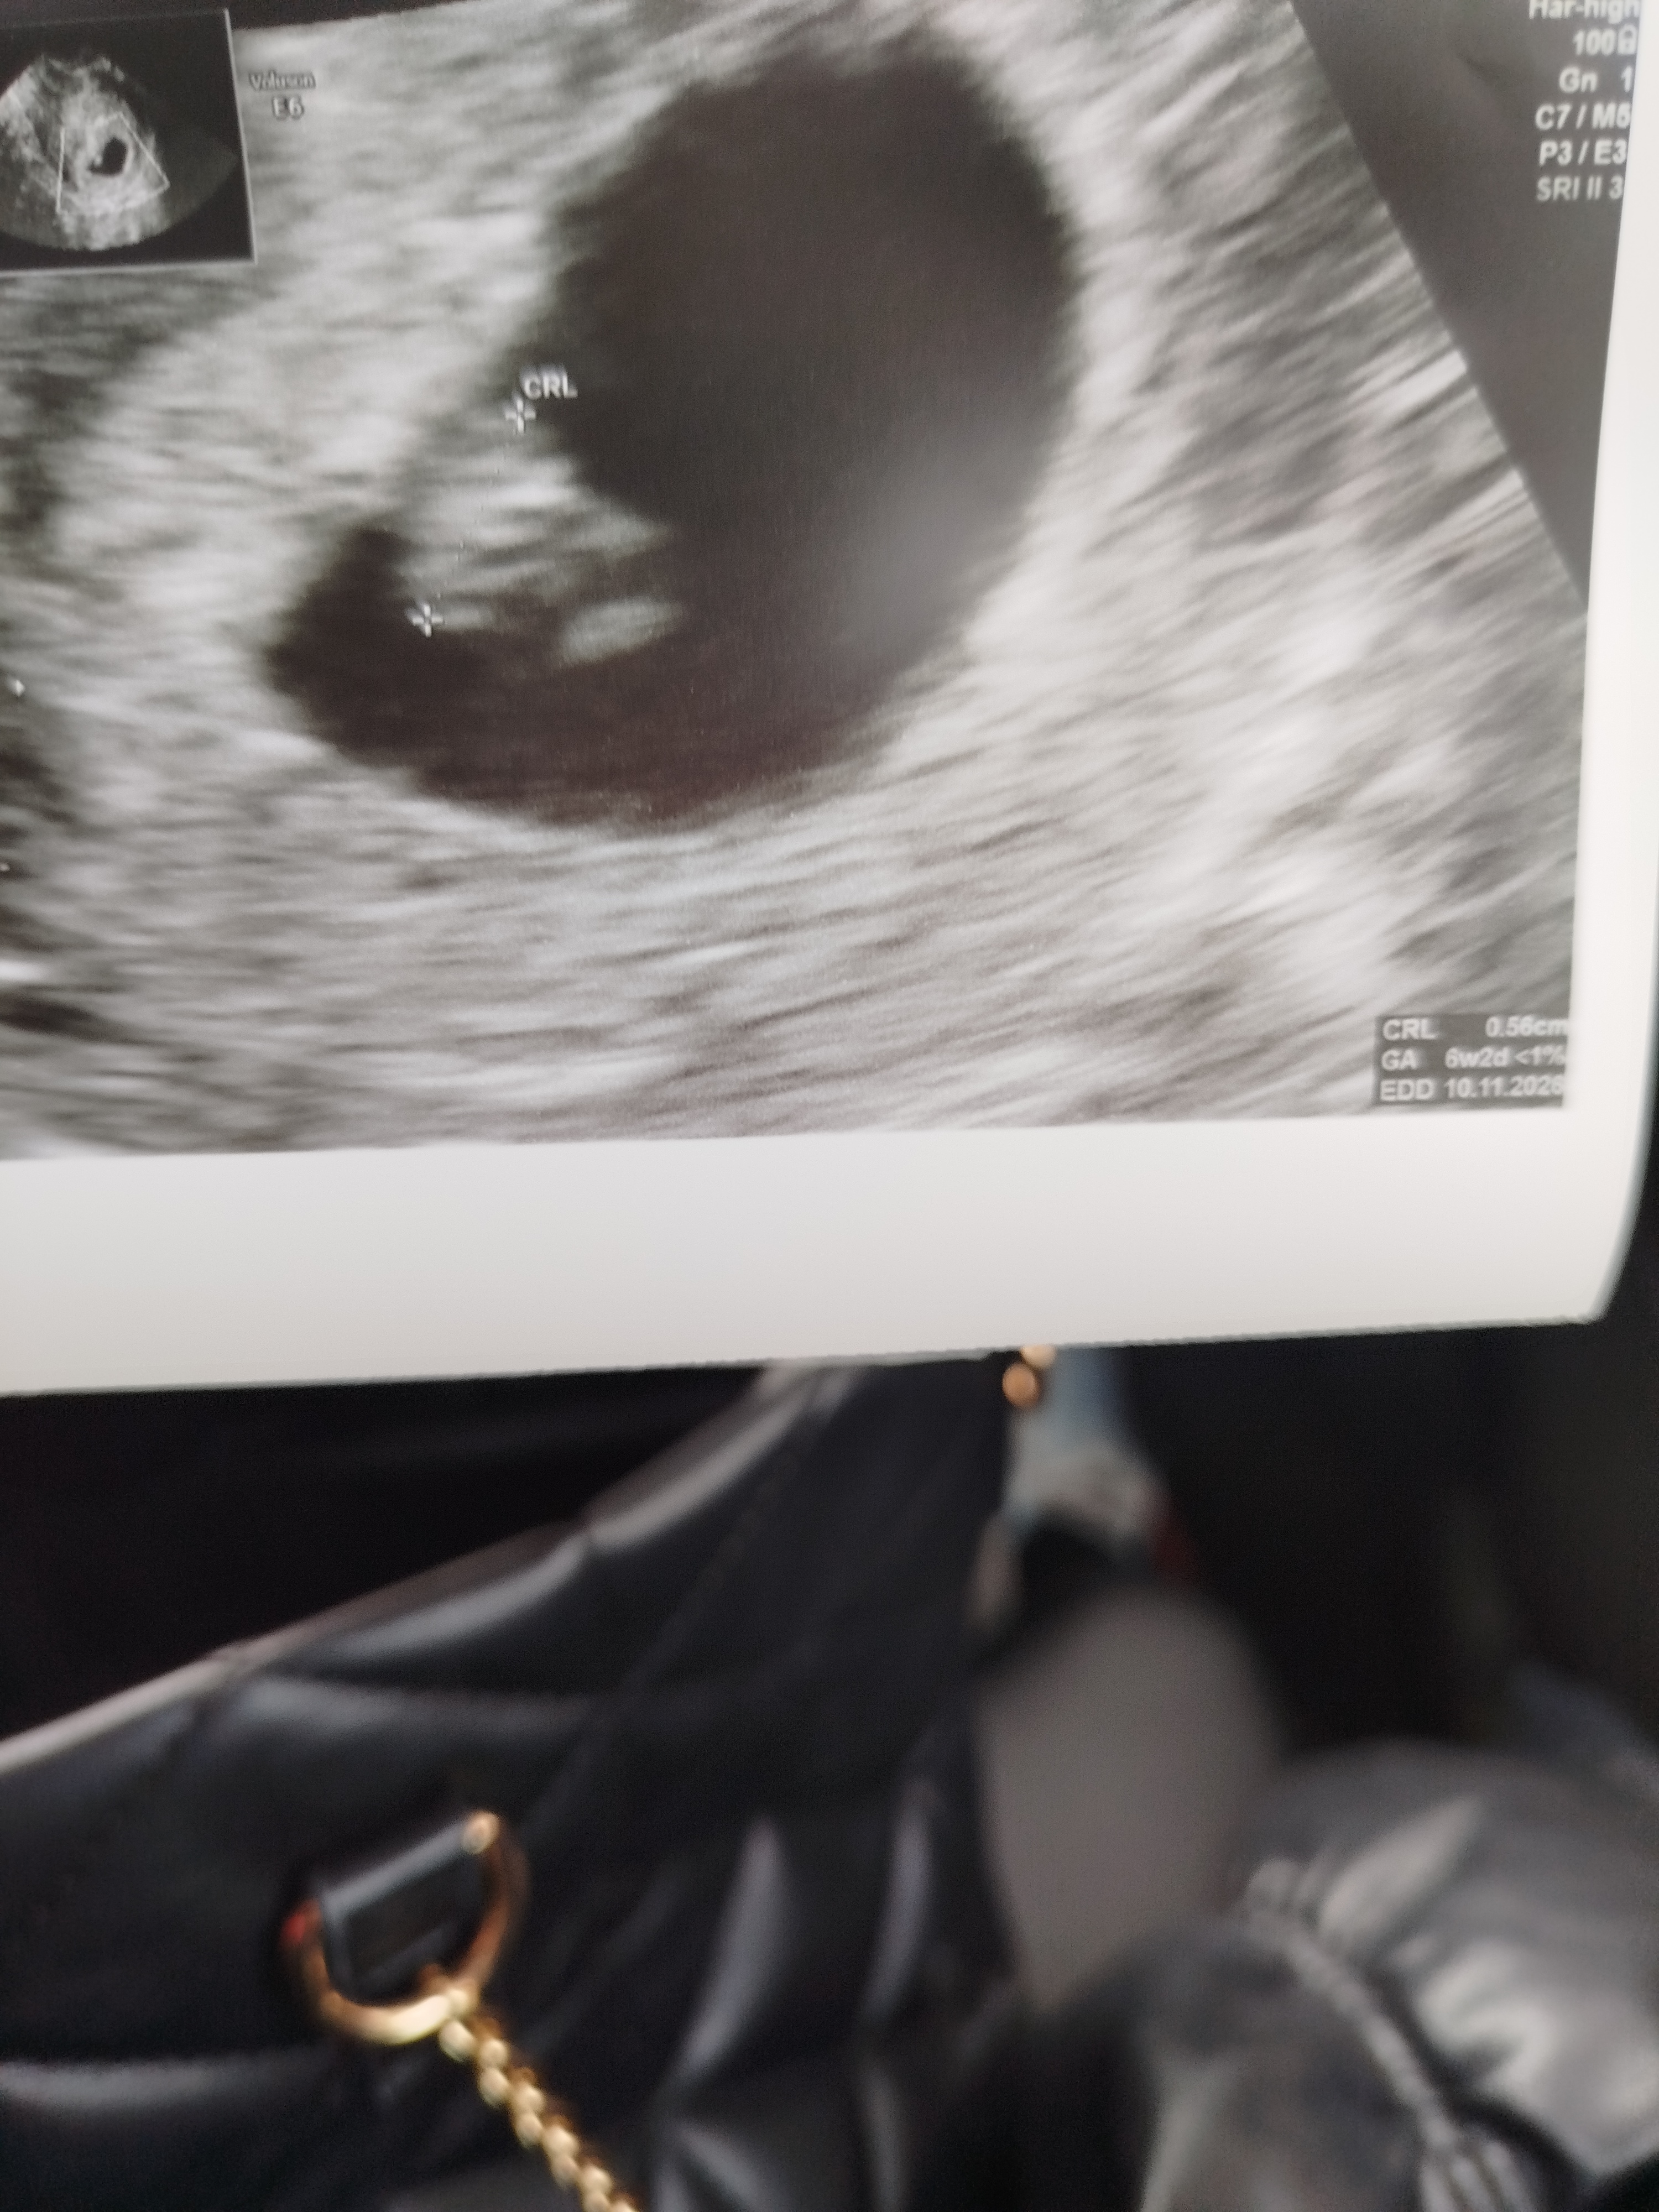

My się meldujemy z kropkiem na pokładzie

Mamy na dzień dzisiejszy z USG 6+2

Serduszko bije 122 bpm 😍